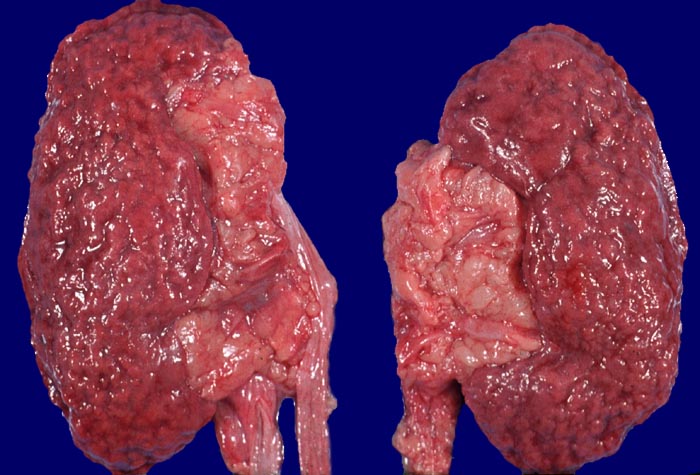

In den beteiligten Organen sind nicht alle Arterien pathologisch verändert und oft ist die Gefässwand nicht zirkulär sondern nur segmental betroffen und die Gefässveränderungen befinden sich in unterschiedlichen Stadien. Folgen der Gefässveränderungen sind Infarkte und Mikroaneurysmata. Die Nieren sind im akuten Stadium oft vergrössert. An der Oberfläche sind Petechien neben unterschiedlich grossen Infarkten erkennbar. Gelegentlich erkennt man auf der Schnittfläche Gefässaneurysmata, thrombosierte Arterien und Papillennekrosen. Im häufigeren chronischen Stadium sind die Nieren verkleinert und aufgrund von Infarktnarben grob gebuckelt.